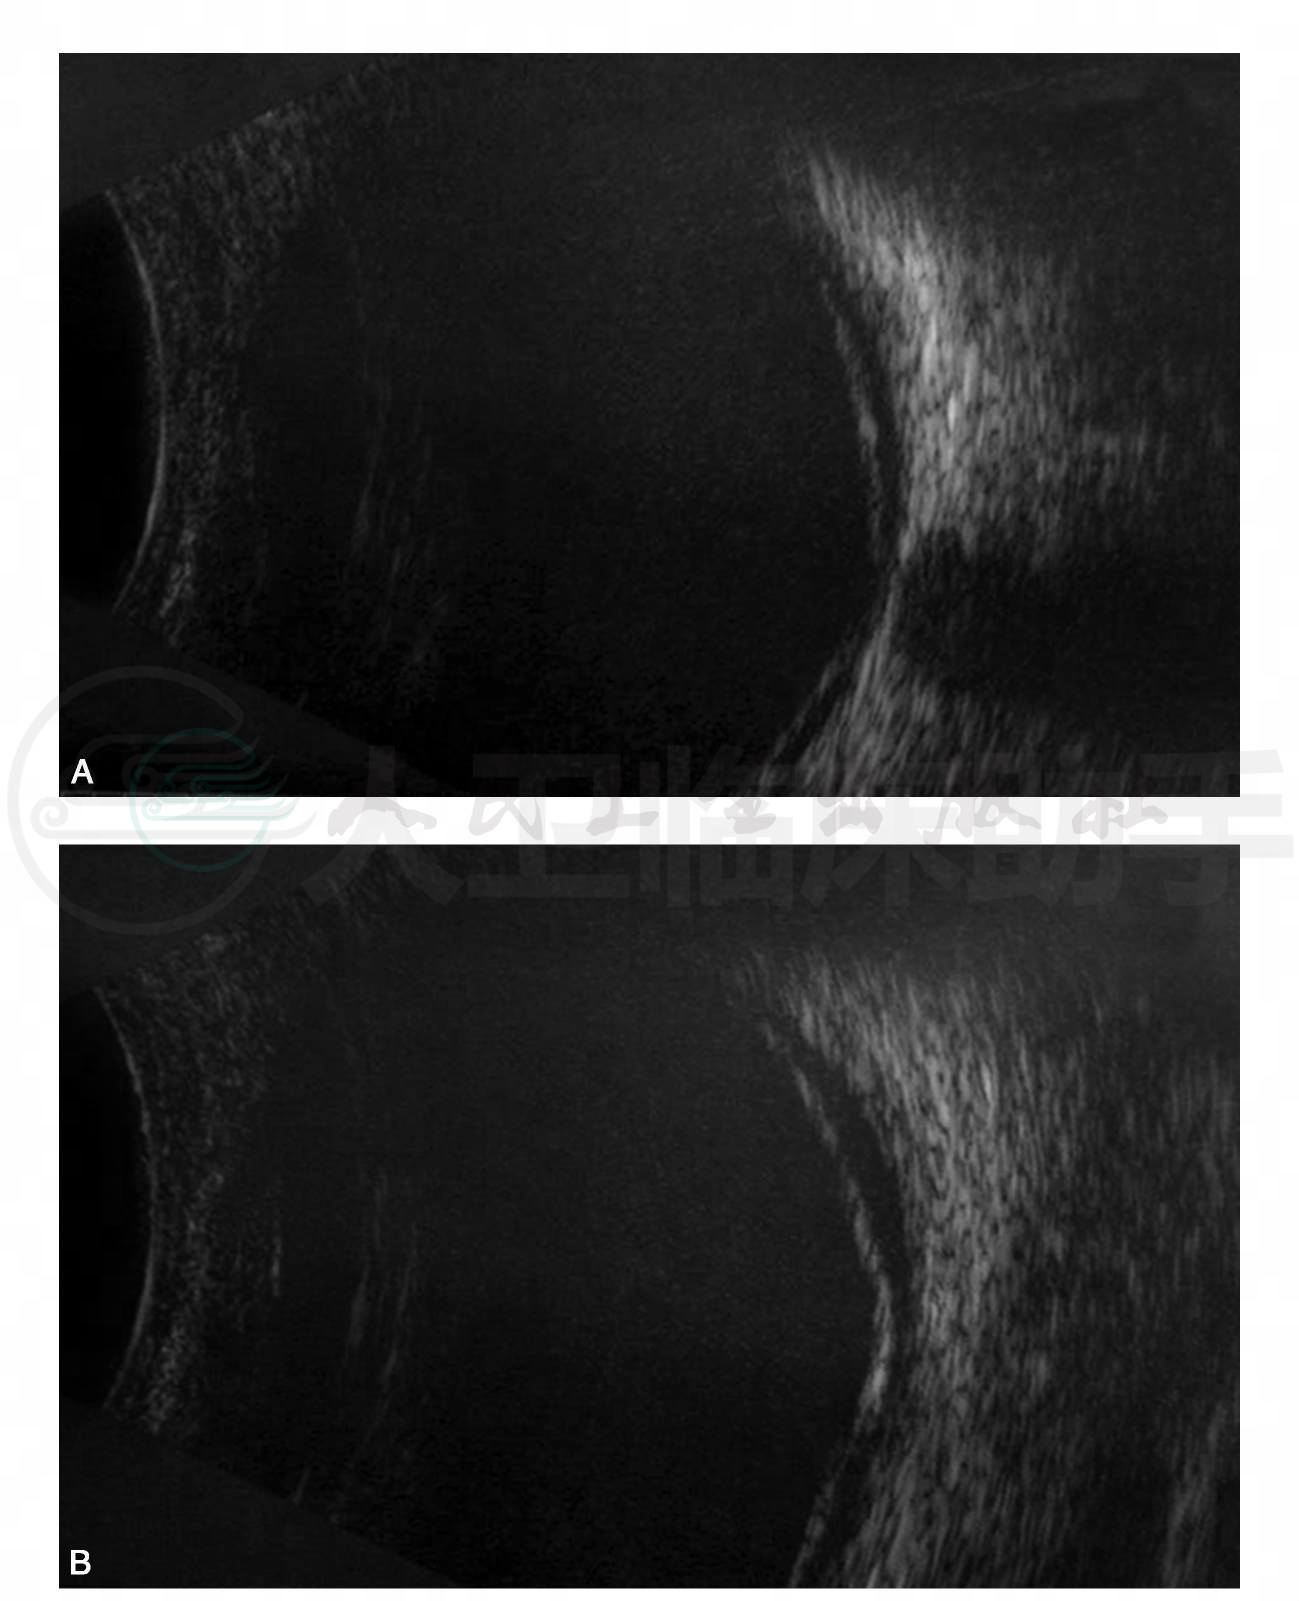

眼科检查:视力右眼0.1,左眼0.3;非接触眼压计测量眼压:右眼12mmHg,左眼16mmHg;双眼外眼及眼前节检查均未见异常;散瞳后间接检眼镜检查:双眼视乳头边界欠清,后极部血管周围明显白鞘,管壁狭窄,全视网膜可见片状黄白色渗出,边界不清,视网膜下出血,并见渗出性视网膜脱离(图 1A,B)。眼科B超检查示双眼视网膜浅脱离(图2A,B)。OCT检查示双眼视网膜脱离及视网膜下高反射物质(图3A,B)。

图2 眼科B超检查示双眼视网膜浅脱离

A.右眼;B.左眼